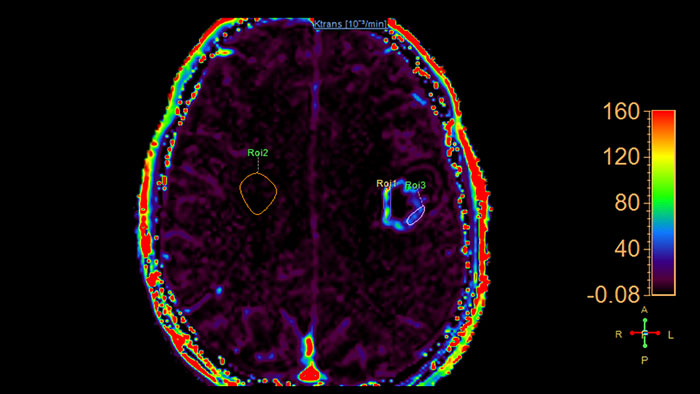

Lesion characterization by reviewing vascular leakage

Designed to visualize T1 weighted DCE 3D datasets and assist in analyzing the tissue response.

Benefits